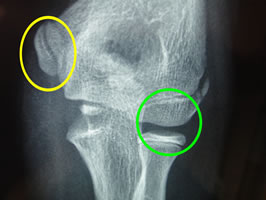

患側(右肘)の拡大画像(↓)です。

赤矢印先の黒い部分が離断性骨軟骨炎です。

黄色矢印先は、先述エコー像内側の黄色矢印に相当します。

健側(左肘)の拡大画像です(↓)

緑丸内部には黒い部分がありません。黄色丸内も正常描出されています。